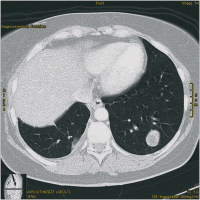

CT

Abbildung 5: CT 3 Monate nach Laserentfernung von Metastasen der rechten Lunge.